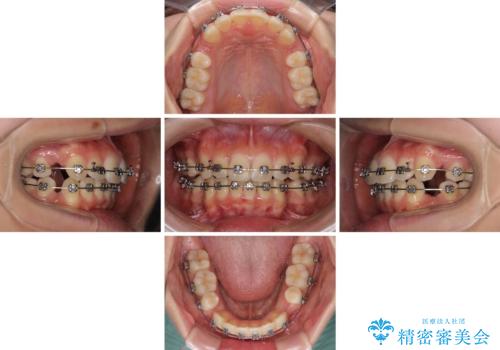

- メタルブラケット

- 1年5ヶ月

上下ともに歯列が前方に突出していたため、上下左右の第一小臼歯4本を抜去し、ワイヤー装置による矯正治療を行うこととしました。

上下左右4本抜歯する場合には、通常2年から2年半ほどの期間を要しますが、僅か1年半で終了することができました。